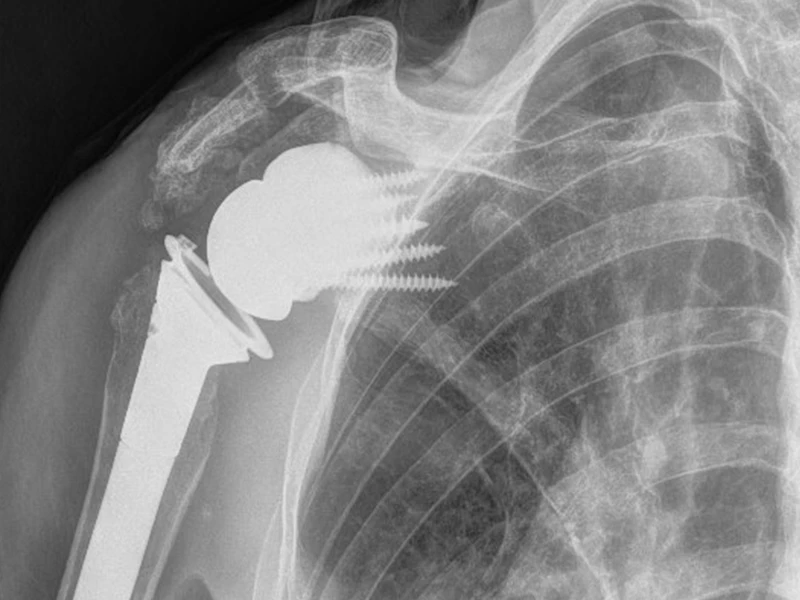

X-ray of a patient's shoulder after undergoing 3D-shoulder arthroplasty.